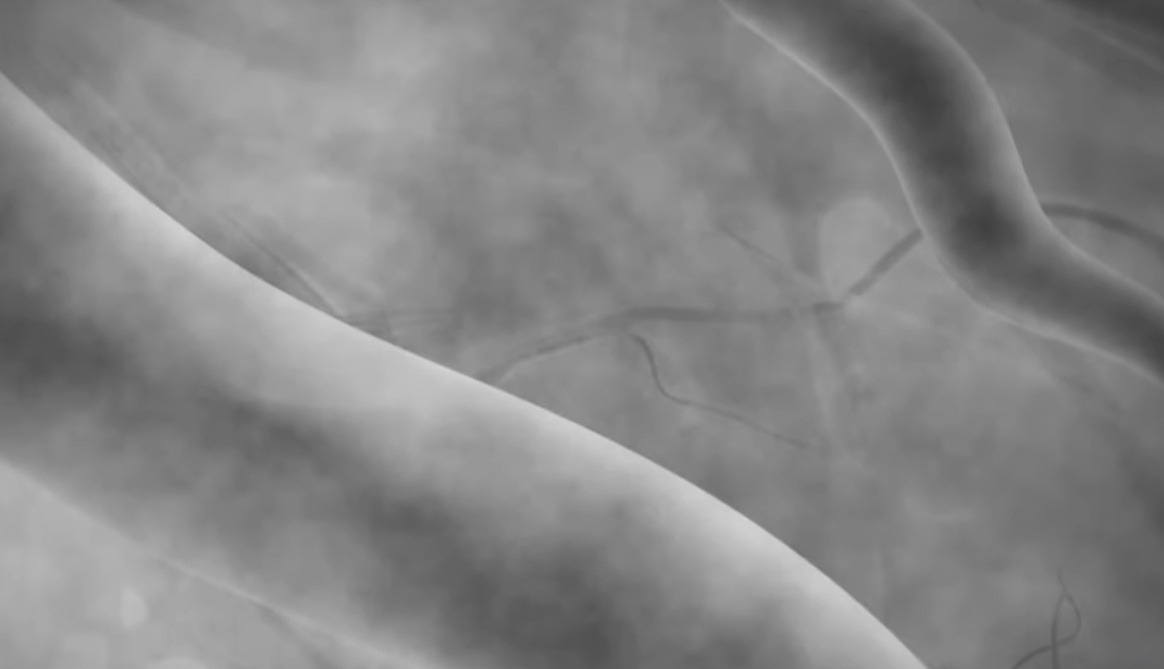

검사는 보통 손목(요골동맥)이나 사타구니 혈관을 통해 가느다란 관을 넣어 심장 혈관까지 이동시킨 뒤, 조영제를 주입하며 X-ray로 촬영합니다.

만약 심한 협착이 발견되면, 같은 자리에서 스텐트 시술(혈관 확장 치료)까지 바로 이어서 시행하는 경우도 많아, 진단과 치료가 한 번에 진행되기도 합니다.